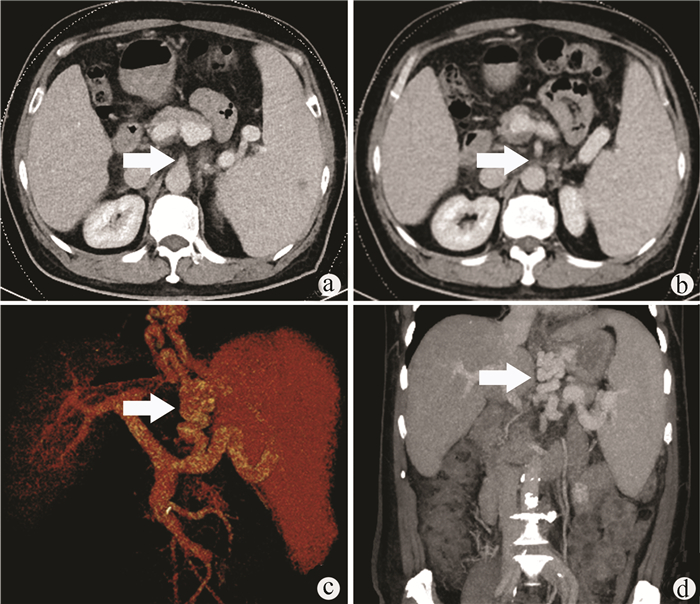

肝滤泡树突细胞肉瘤1例报告

李晨光, 贾继尧, 孙栾彪, 高硕徽

2022, 38(1): 174-176. DOI: 10.3969/j.issn.1001-5256.2022.01.029

摘要(1626) HTML (458) PDF (2854KB)(70)

摘要: